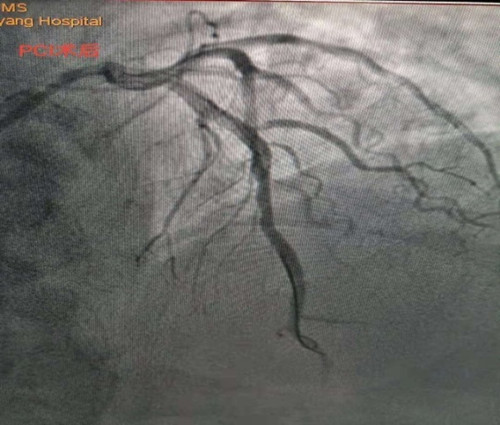

李新国主任为蒿大叔做了急诊冠脉造影检查,提示前降支近中段90%狭窄, D1开口99%狭窄,可见血栓影,结合术前心脏超声检查发现患者心脏腱索水平以下左室前间壁、前壁、前侧壁运动搏幅减低,梗死范围大,考虑罪犯血管为前降支近中段,在前降支近中段植入了一枚支架,开通闭塞血管。经过1个多小时的抢救,蒿大叔总算从鬼门关被救了回来了。